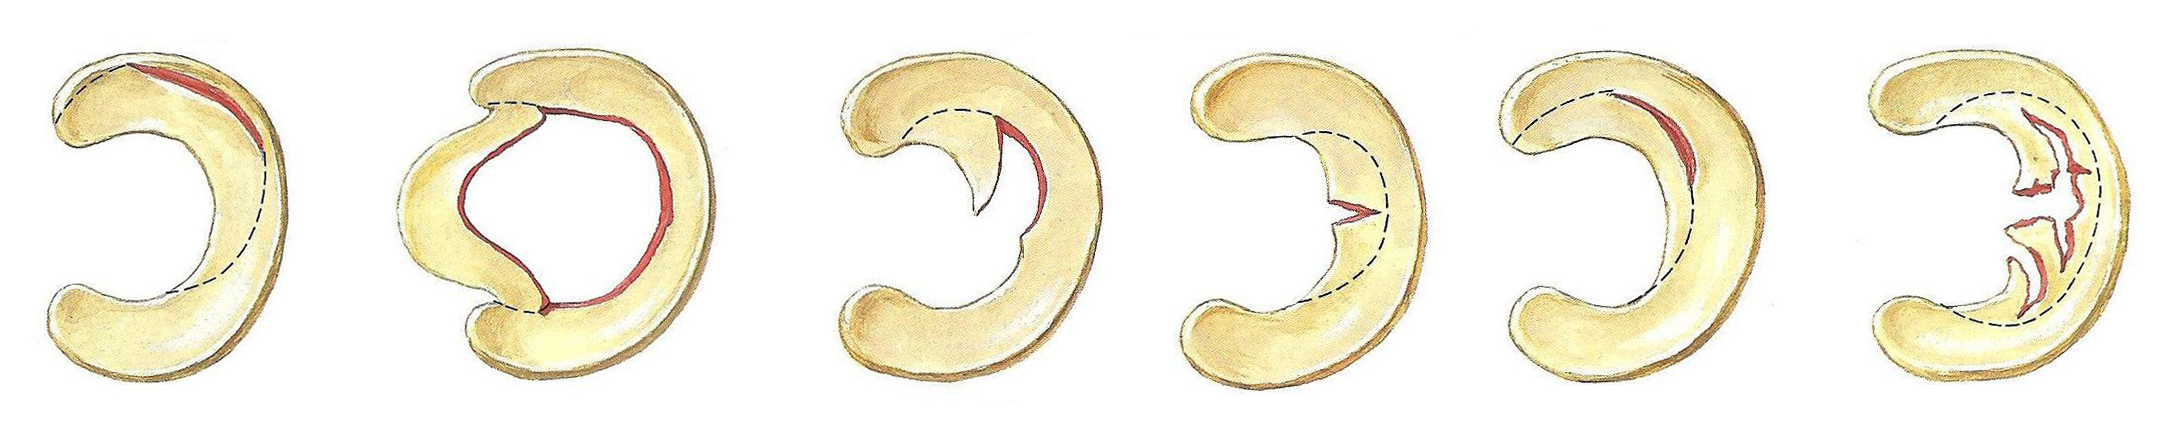

Υπάρχουν διαφορετικά είδη ρήξεων (εικόνα 4). Συχνότερη είναι η περιφερική ρήξη.

Οι εκτεταμένες περιφερικές ρήξεις παρεκτοπίζονται στο κέντρο του γόνατος μπλοκάροντας τη λειτουργία του και λόγω της μορφής τους ονομάζονται “ρήξεις δίκην λαβής κάδου”. Άλλα είδη ρήξεως είναι η κάθετη ακτινωτή, η οριζόντια, η κατ’εφαπτόμενη ρήξη ή Flap και αρκετά συχνές οι ακαθόριστης μορφής, όπως είναι οι εκφυλιστικές.

Η μορφολογία της τραυματικής ρήξης είναι συχνότερα περιφερικού τύπου, περισσότερο ή λιγότερο εκτεταμένη, που συχνά παρεκτοπίζεται και προκαλεί εμπλοκή στη λειτουργία του γόνατος, ενώ στις εκφυλιστικές η μορφή της ρήξης είναι κυρίως ακαθόριστη.